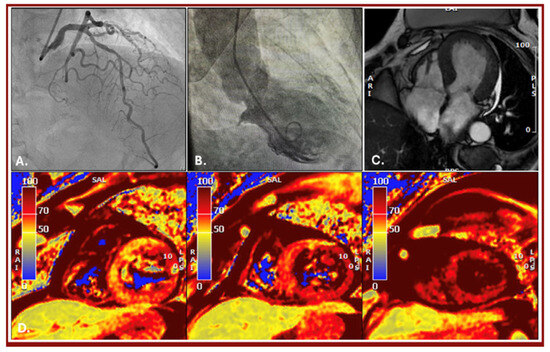

Multimodality Imaging in the Diagnosis of an Early Tako-Tsubo Syndrome Recurrence

by Maria Letizia Berloni, Andrea Daniele Annoni, Marco Moltrasio, Andrea Baggiano and Gianluca Pontone

We report the case of an 80 yo female patient with cardiovascular risk factors and previous diagnosis of Tako-Tsubo syndrome, who was referred to our institution one year after a previous diagnosis, due to symptoms suggestive of acute coronary syndrome (SCA) after severe [...] Read more.

We report the case of an 80 yo female patient with cardiovascular risk factors and previous diagnosis of Tako-Tsubo syndrome, who was referred to our institution one year after a previous diagnosis, due to symptoms suggestive of acute coronary syndrome (SCA) after severe emotional stress. After ruling out suspected CAD by cardiac computed tomography (CCT) and subsequent invasive coronary angiography (ICA) confirming no significant stenosis but presence of vulnerable plaque, the patient underwent further investigation by cardiac magnetic resonance (CMR) that confirmed a clinical picture compatible with recurrence of Tako-Tsubo syndrome. Our case underlines the importance of multimodality imaging to guide diagnosis and treatment in this specific clinical scenario. Full article